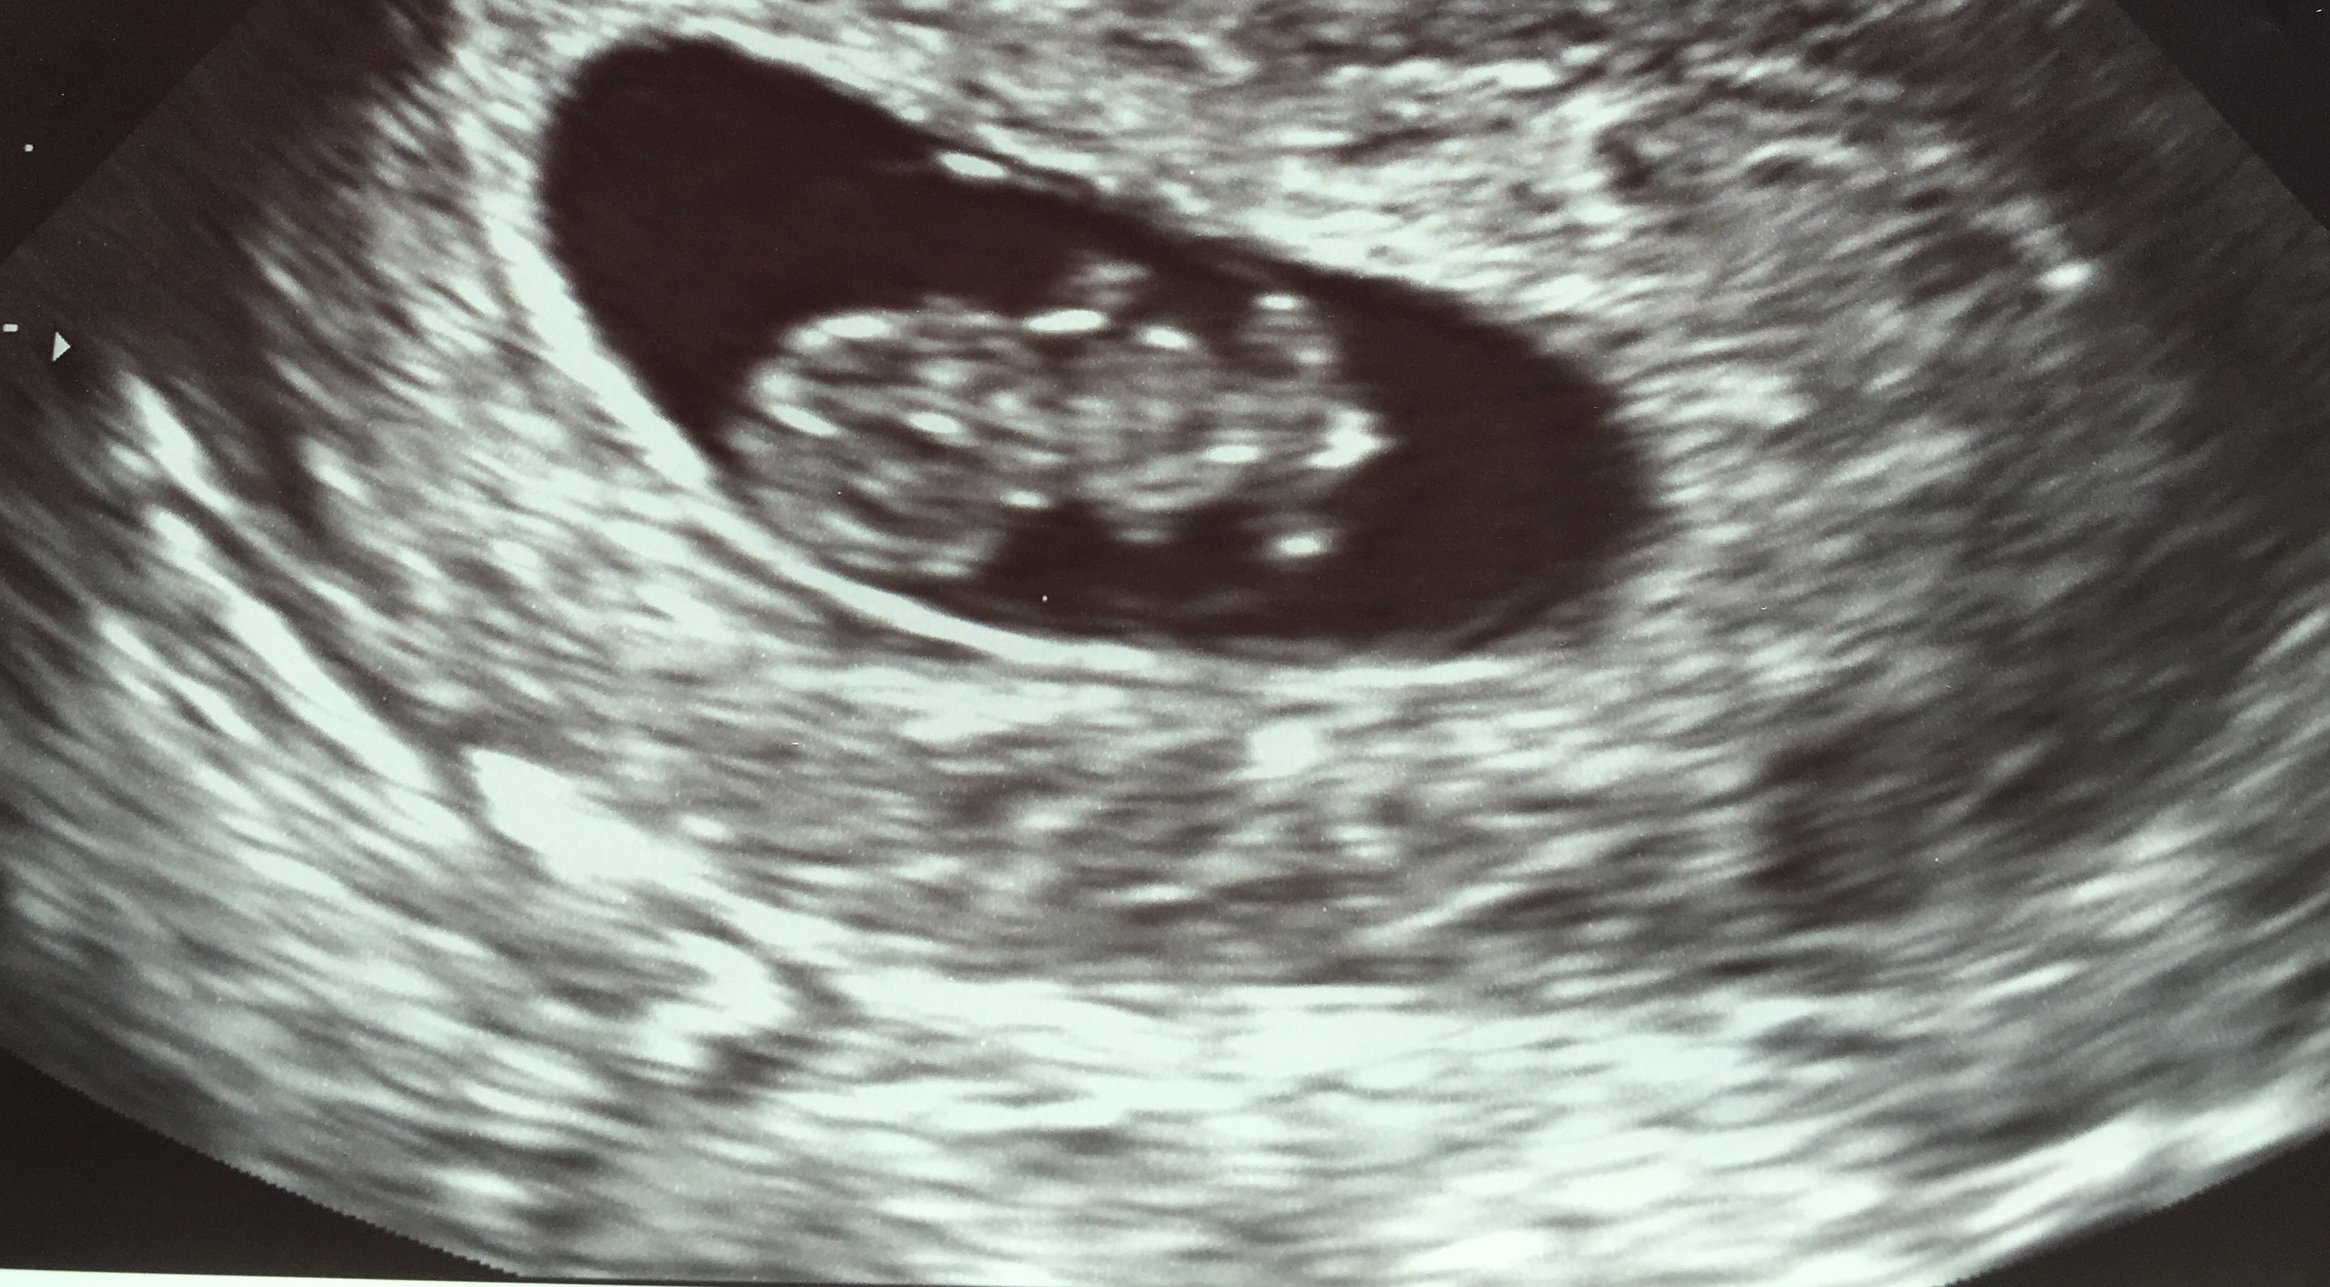

3. Any upcoming appointments and/or updates from recent appointments? Saw the baby today!!! Picture below! Measuring 8w5d and heartbeat 163. Last time baby looked like a dot but this time more baby-like!

4. Questions/concerns? I'll come back later to respond to you all when I have more time but just wanted to share! So excited

And your ultrasound is sooooo cute!!!!

kyersten Yay! Congratulations! So exciting to see an ultrasound pic that's further along.

@kyersten Congrats! Looks more like a froggie than a tadpole now!